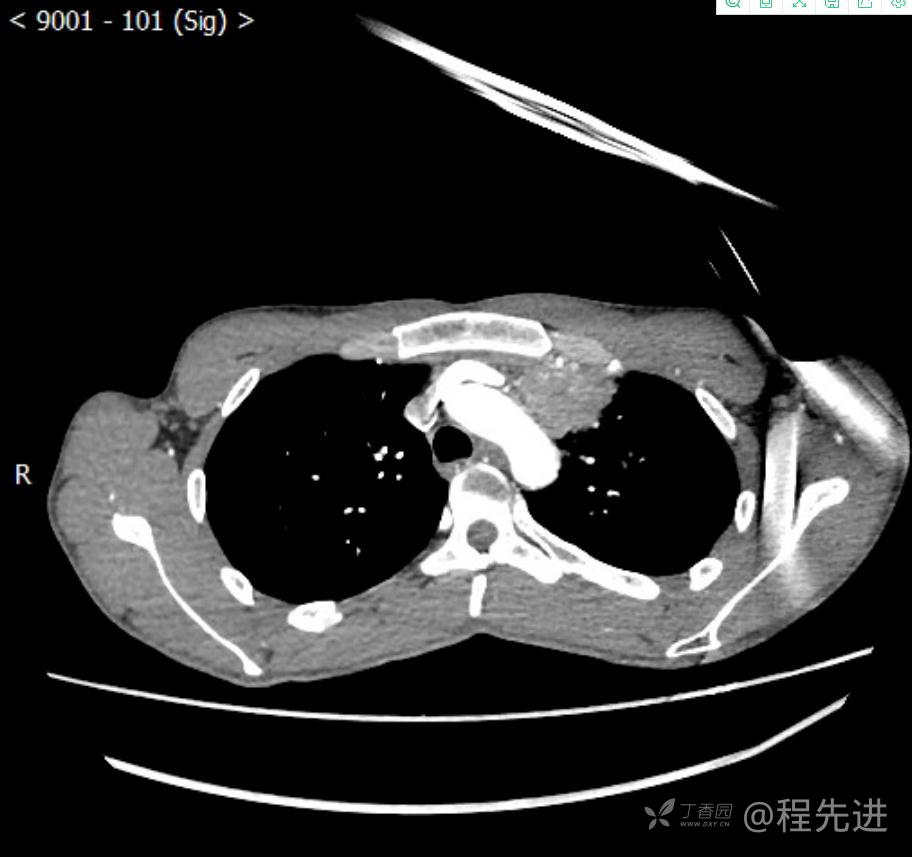

主诉:反复咳嗽1月,发现“纵隔”占位半月,乏力10余天。

现病史:患者1月前无明显诱因出现咳嗽,以夜间为著,伴有少量白痰,无发热,无胸痛、咯血,无痰中带血,未予重视,半月前外院行胸部CT检查发现“左前上纵隔”占位,未予进一步检查及治疗。近10余天自觉乏力,逐渐加重。